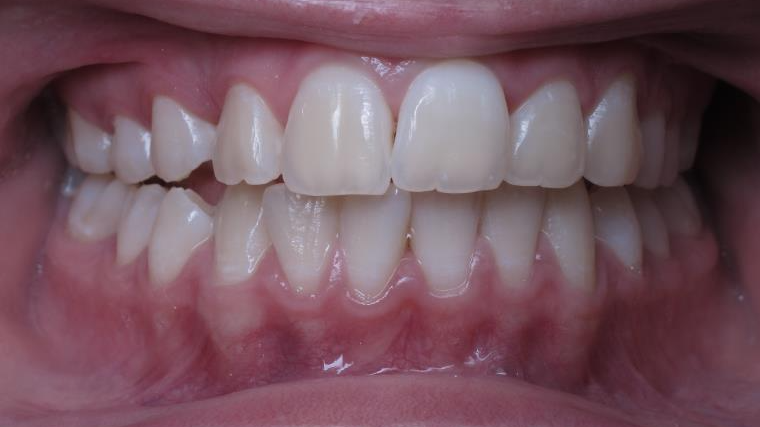

surveillance évolution de la dentition pendant 4 ans

surveillance de la dentition par gouttieres nocturne

bilan début et fin de traitement